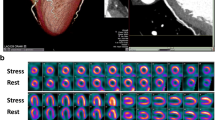

CA and MPI (SPECT or PET) were successfully performed in all patients (n = 150) (Figs. 1 and 2). CA revealed 122 patients (81%) to have CAD (defined as at least one coronary lesion with luminal narrowing ≥50%). Patients undergoing SPECT or PET did not differ among each other with regard to age, gender, BMI, cardiovascular risk, history of myocardial infarction, and particularly not with regard to coronary findings (Tables 2 and 3).

Stress and rest SPECT images reveal an irreversible inferior basal perfusion defect (open arrow heads), representing a myocardial scar. At stress an additional minor lateral perfusion defect (solid arrow heads) is indicative of minor ischemia. VLA: vertical long axis; HLA: horizontal long axis; SA: short axis